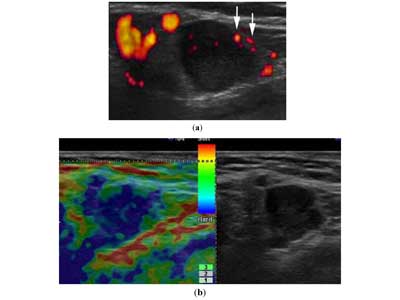

- Η ελαστογραφική εικόνα επιπροβάλλει σε B-mode εικόνα

- Λαµβάνεται ένα ζεύγος εικόνων. ∆εξιά προβάλλει η κλασική υπερηχογραφική εικόνα και αριστερά η ελαστογραφική